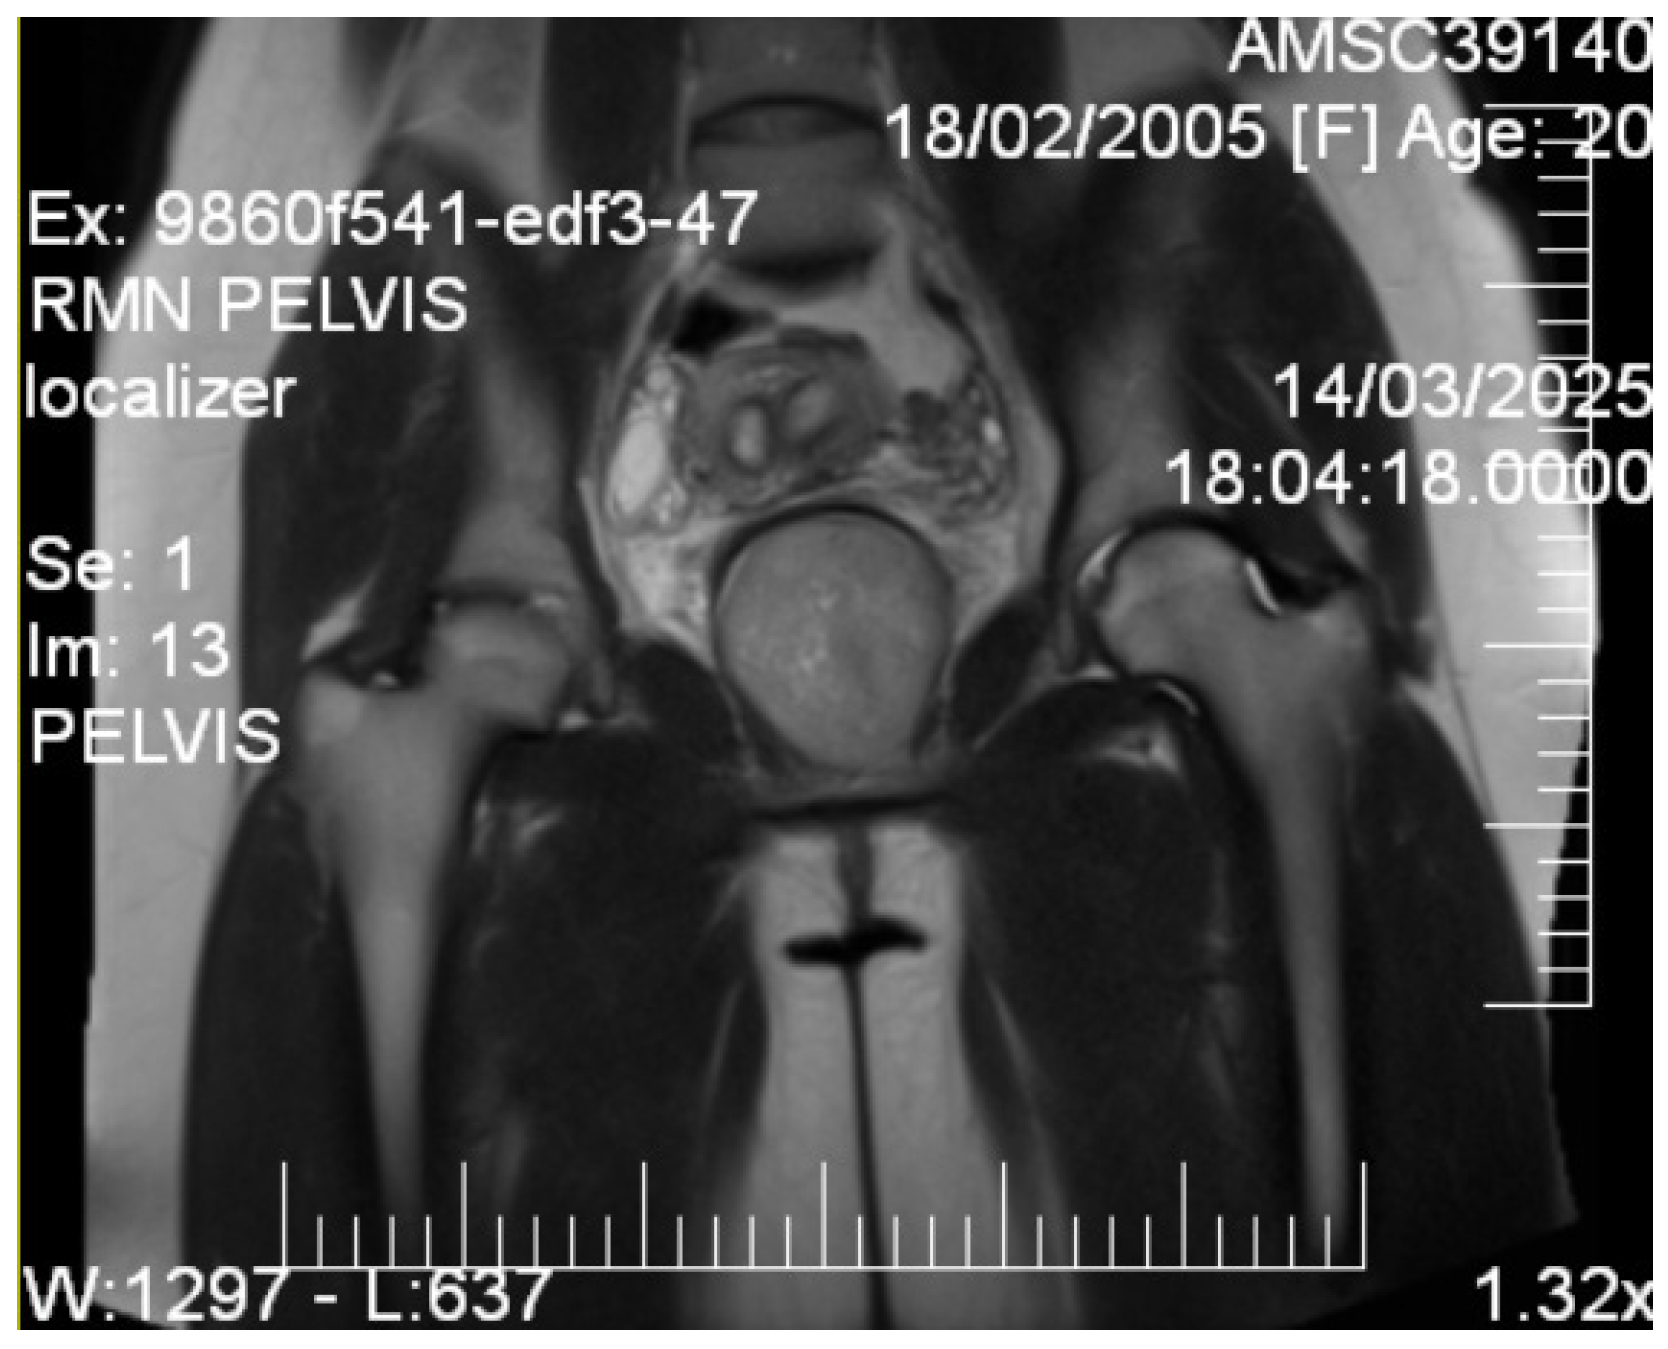

2.4. Imaging Studies

3.1. Imaging Characteristics and Diagnostic Precision

- MRI is decisive in characterizing tissues.